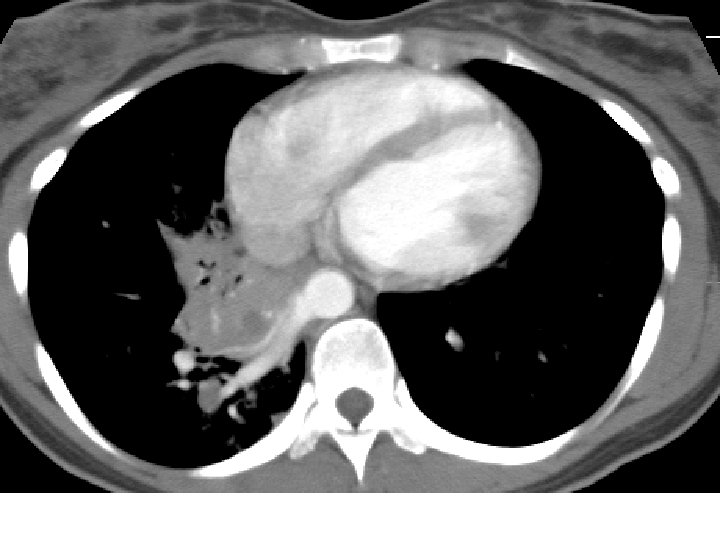

Final Diagnosis Intralobar Pulmonary Sequestration 8152005 History of

Final Diagnosis Intralobar Pulmonary Sequestration

History of recurrent pneumonia

Intralobar Pulmonary Sequestration (ILS) Characteristics • More common type • May present at any age • Generally as recurrent infection • No sexual predominance • Almost exclusively affects lower lobe • Arterial supply: descending aorta • Venous drainage: pulmonary veins